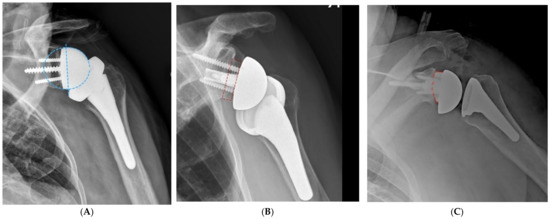

Stems that do not engage the cylindrical portion of the endosteal canal can easily be misaligned. Excessive valgus or varus will lead to a poor humeral head position in anatomic arthroplasty. Similarly, poor alignment can lead to a reverse polyethylene that is excessively horizontal with an increased risk of notching, or to a more vertical polyethylene that may facilitate dislocation. Certain short stems have been designed with just enough length to avoid malalignment [17]. Stemless prostheses are also at risk for malalignment (Figure 1). As such, care must be taken to optimize the humeral head cut to minimize the chances of malalignment with ultrashort stem and stemless prostheses.

Figure 1.

Ultrashort stems (A) and stemless prostheses (B) are at increased risk for malalignment.

The preparation of the metaphysis for modern components that rely on peripheral fixation typically aims to place the component “bowl” so that it will leave 2–4 mm of cancellous bone between the component and the cortical rim of the metaphysis (Figure 8). A wider distance may be advantageous in patients with a stronger bone that does not require maximizing peripheral fixation. The guide pin for the reaming of the metaphysis may be centered using a trial humeral head or sizing discs.

Figure 8.

Primary component stability may be optimized by the implant fit at the periphery of the proximal humerus, within 2–4 mm of the cortical rim. (A), Sizing disk; (B), Trial; (C), Humeral component.